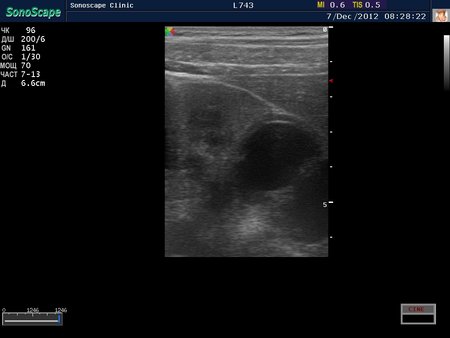

Пациент с подтвержденным туберкулезом почки

2.jpg

Видим длительно существующий гидронефроз вследствие процесса в области лоханочно-мочеточникового сегмента (видео 1), с утолщением стенок ЧЛС и истончением паренхимы почки - наиболее частая причина у взрослых - туберкулез.